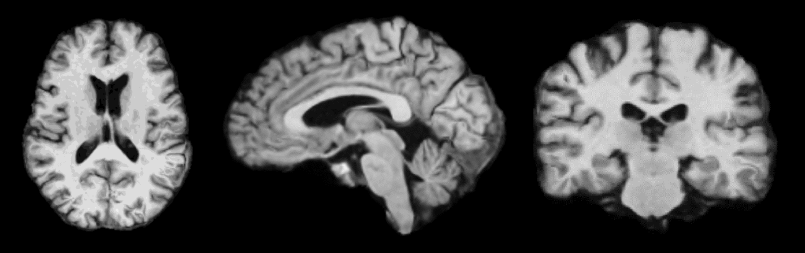

We present a semi-parametric generative model for predicting anatomy of a patient in subsequent scans following a single baseline image. Such predictive modeling promises to facilitate novel analyses in both voxel-level studies and longitudinal biomarker evaluation. We capture anatomical change through a combination of population-wide regression and a non-parametric model of the subject’s health based on individual genetic and clinical indicators. In contrast to classical correlation and longitudinal analysis, we focus on predicting new observations from a single subject observation. We demonstrate prediction of follow-up anatomical scans in the ADNI cohort, and illustrate a novel analysis approach that compares a patient’s scans to the predicted subject-specific healthy anatomical trajectory. The code is available at https://github.com/adalca/voxelorb.

We present a method for predicting anatomy based on external information, including genetic and clinical indicators. Specifically, given only a single baseline scan of a new subject in a longitudinal study, our model predicts anatomical changes and generates a subsequent image by leveraging subject-specific genetic and clinical information. Such voxel-wise prediction opens up several new areas of analysis, enabling novel investigations both at the voxel level and at the level of derivative biomarker measures. For example, voxel level differences between the true progression of a patient with dementia and their predicted healthy anatomy highlight spatial patterns of disease. We validate our method by comparing measurements of volumes of anatomical structures based on predicted images to those extracted from the acquired scans.

Our model describes the change from a single (or baseline) medical scan in terms of population trends and subject-specific external information. We model how anatomical appearance changes with age on average in a population, as well as deviations from the population average using a person’s health profile. We characterize such profiles non-parametrically based on the genotype, clinical information, and the baseline image. Subject-specific change is constructed from the similarity of health profiles in the cohort, using a Gaussian process parametrized by a population health covariance. Given the predicted change, we synthesize new images through an appearance model.